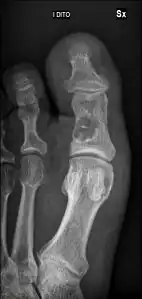

- Unprovoked break in big toe, with "fallen leaf" sign.